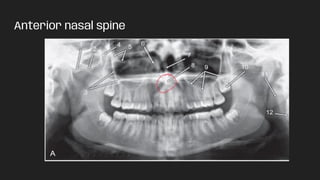

● Anterior nasal spine

Anterior nasal spine